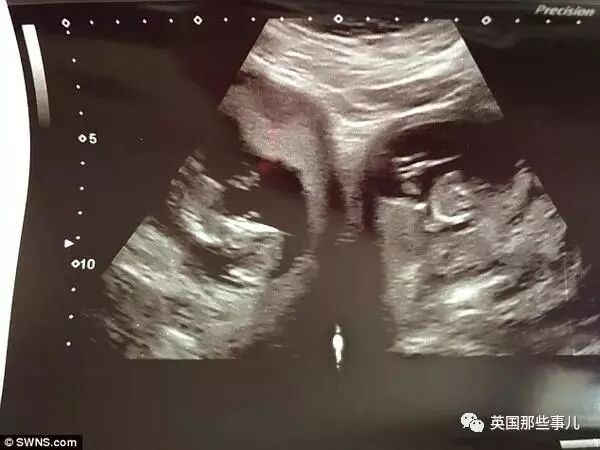

最近,英国一对夫妇家中迎来了一件喜事,妻子詹妮弗生下了一对双胞胎~但是,他们与一般的双胞胎很不一样,因为他们从妈妈两个不同的子宫中诞生的。

在双胞胎降生之前,詹妮弗已经有了一个8岁大的女儿,在她第一次怀孕的时候,并没有检查出任何的异常。直到去年的12月份,詹妮弗发现自己又怀孕了,经过产检后发现居然是一对双胞胎,两人非常激动,也一直期待着宝宝的到来。可就在今年2月份的产检中,医生发现了异样,原来詹妮弗属于双子宫妈妈!且所谓的双胞胎宝宝则分别在她的两个子宫内!她表示:“我的身体让我感到惊讶。”